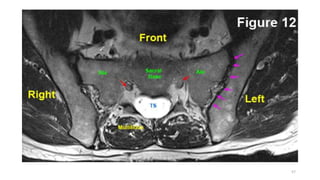

SULCI & GYRI

SULCUS IS THE DEPRESSION [VALLEYS]

AND

GYRUS IS THE RIDGE [HILLS]

Fissure/sulcus Importance

• Interhemispheric fissure • Separates two lobes

 Sylvian fissure/ Lateral

Sulcus

 Frontal to temporal

 Central sulcus  Frontal to parietal

 Callosal sulcus

 Cingulate sulcus

 Interparietal sulcus

 Parieto occipital sulcus

 Calcarine sulcus

12

6

Interhemispheric

fissure

1

3

2

4

5

Superior frontal

Pre central sulcus

Central sulcus

Post central

IPIO

Interhemispheric fissure